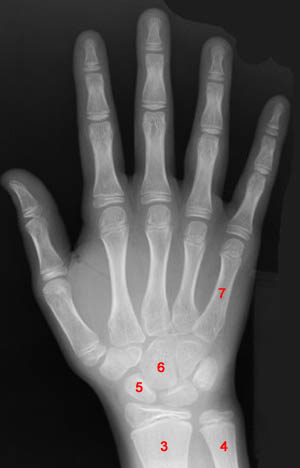

Questions 3-7: Please refer to the following image.

3) Identify the object labeled "3" in the above image.

4) Identify the object labeled "4" in the above image.

5) Identify the object labeled "5" in the above image.

6) Identify the object labeled "6" in the above image.

7) Identify the object labeled "7" in the above image.